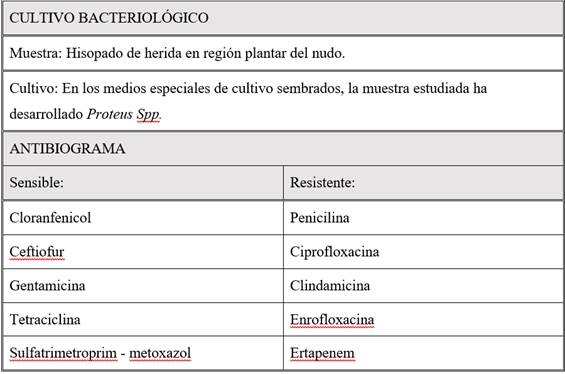

Obtenidos los resultados del cultivo y antibiograma, se confirma crecimiento bacteriano de Proteus spp (tabla 1).

Tabla 1: Resultados obtenidos del cultivo y antibiograma de la muestra tomada, con hisopo estéril, de zonas profundas de la herida. Con la evaluación clínica, estudios de imagen y resultados de laboratorio se puede decir que la herida tuvo una evolución hacia una tendosinovitis séptica con posterior osteítis séptica de los huesos sesamoideos como diagnóstico definitivo.